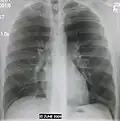

Normal lateral CXR -

AP CXR showing pneumonia of the lingula of the left lung -

Right upper lobe pneumonia as marked by the circle. -

Left upper lobe pneumonia with a small pleural effusion.